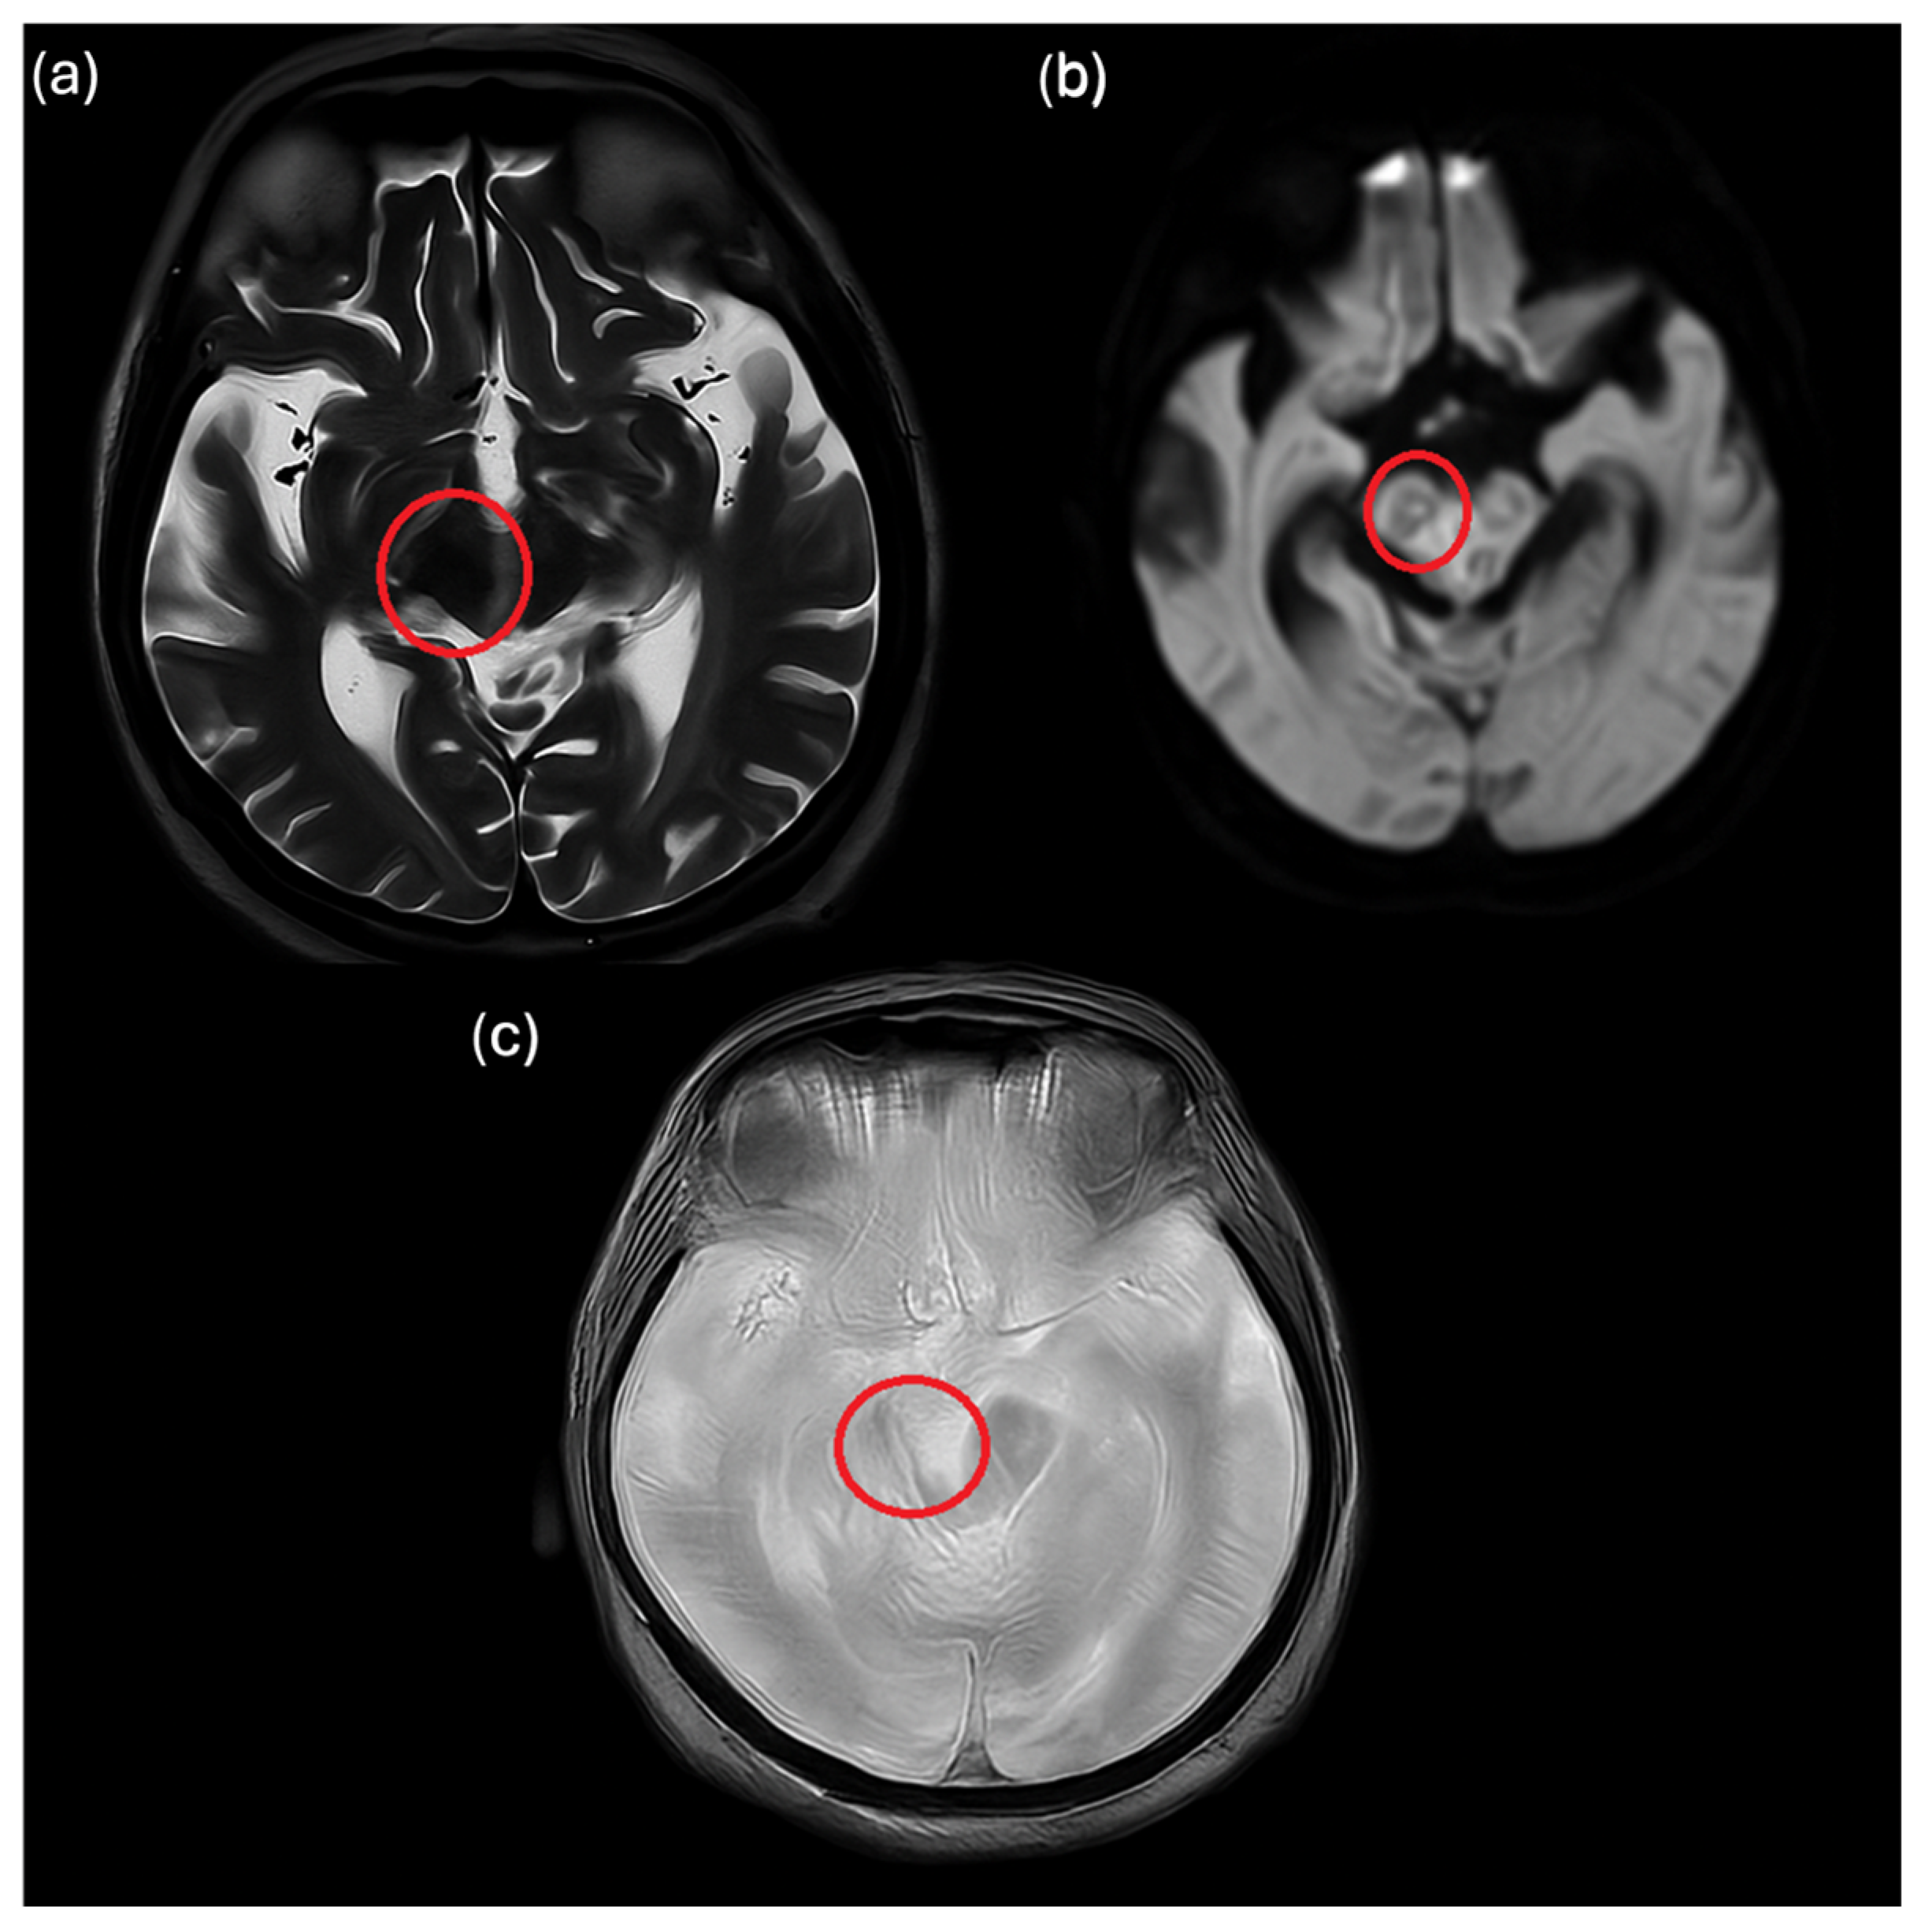

2. Case Description